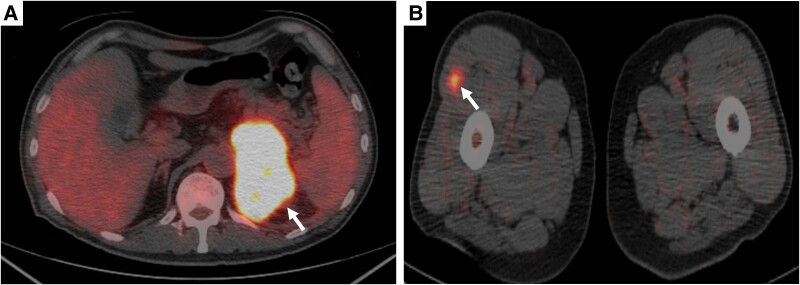

原发性恶性淋巴瘤起源于肾上腺,尤其是起源于t细胞,是非常罕见的。我们报告一例原发性单侧肾上腺间变性大细胞淋巴瘤。一名64岁的日本男性最初表现为疲劳和食欲不振。计算机断层成像显示单侧肾上腺肿块伴多器官侵犯,对肾上腺癌的鉴别提出了挑战。对右外侧股肌转移部位进行活检,免疫组化显示肿瘤细胞CD30和CD56呈阳性,CD3、CD15、CD20、CD43、穿孔素、颗粒酶B、上皮膜抗原和间变性淋巴瘤激酶呈阴性。最终,患者被诊断为原发性单侧肾上腺间变性大细胞淋巴瘤。虽然他对化疗取得了完全缓解,但在完全缓解后4个月,他因胆囊炎和淋巴瘤复发而死亡。

Primary malignant lymphomas originating in the adrenal gland, particularly of T-cell origin, are extremely rare. Here we present the primary unilateral adrenal anaplastic large cell lymphoma case. A 64-year-old Japanese male initially presented with fatigue and appetite loss. Computed tomography imaging revealed a unilateral adrenal mass with multiorgan invasion, posing challenges in differentiation from adrenal carcinoma. A biopsy from the metastatic site in the right lateral vastus muscle was obtained, and immunohistochemistry revealed that tumor cells were positive for CD30 and CD56 and negative for CD3, CD15, CD20, CD43, perforin, granzyme B, epithelial membrane antigen, and anaplastic lymphoma kinase. Ultimately, the patient was diagnosed with primary unilateral adrenal anaplastic large cell lymphoma. Although he achieved complete response to chemotherapy, he died 4 months after complete response due to cholecystitis and lymphoma recurrence.